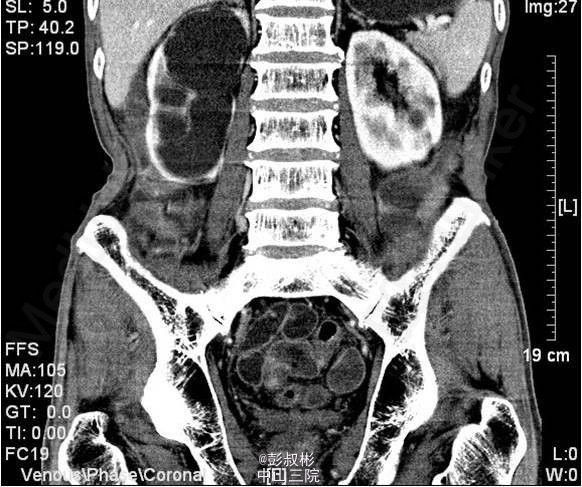

3、既往病史:既往“高血压”病史20年余,自服硝苯地平。“脑梗死”病史半年余,规律服用抗凝药物。 4、入院查体:无明显阳性体征。 实验室检查: 2015-01-11 肌酐101.2umol/L 。 2015-01-13总前列腺特异性抗原1.1ng/ml,游离前列腺特异性抗原0.3ng/ml。 2015-01-15 白细胞总数3.21x10E9/L,红细胞总数2.61x10E12/L,血红蛋白浓度78g/L,肌酐131umol/L ,白蛋白27g/L。 影像学检查: 2014-12-30心电图:完全性右束支传导阻滞。 2014-12-30全腹螺旋CT 检查所见:1、前列腺增生并钙化,建议MRI增强进一步检查除外合并肿瘤性病变。2、右侧盂管交界处结石并重度梗阻性肾积水,右肾结石;左肾多发钙化灶;左肾多发囊肿。3、慢性胆囊炎。4、双肺下叶多发小结节。 2015-01-14核素肾动态显像+GFR双血浆测定:右肾灌注、功能重度受损。左肾灌注正常,功能中度降低。肾小球滤过率:左肾为23.4ml/min,右肾为9.0ml/min。 2015-01-15彩超心脏:二尖瓣反流(轻度)。三尖瓣反流(轻度)。左室收缩功能正常。左室舒张功能减退。

5、目前诊断:1、右侧重度肾积水2、双侧肾结石3、左肾多发囊肿4、慢性胆囊炎